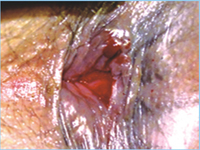

产生肛裂的原因有哪些?福州医博肛肠医生向您解释:有以下几种学说,给大家做个参考。肛裂的原因主要有哪些,在肛裂的发病因素中,便秘是极大的祸根。患者用力排出干燥粪块,必然会使肛门承受较大压力,产生裂口、胀肿等一系列病理改变。一些不良的排便习惯比如厕所看书或者吸烟,这都容易造成肛门直肠内瘀血而诱发疾病。肛裂常见于于青壮年,儿童也可发生,老年人较少。大部分肛裂是由于便秘造成的,便秘促使大便干硬密结,难以排泄,患者用力过猛,将肛门周围皮肤撑裂,产生的创面由于反复感染而不能愈合,逐渐演变成肛裂。肛裂主要症状就是便血、疼痛和瘙痒。如果大家有什么不明白的,还要到专业医院去。

医生提醒:肛裂经久不治或治疗不当,会导致溃疡加深,会形成瘢痕性肛管狭小,乳头肥大,哨兵痔,甚至继发肛隐窝炎和内盲瘘,因此,及时到专业肛肠医院治疗很关键。